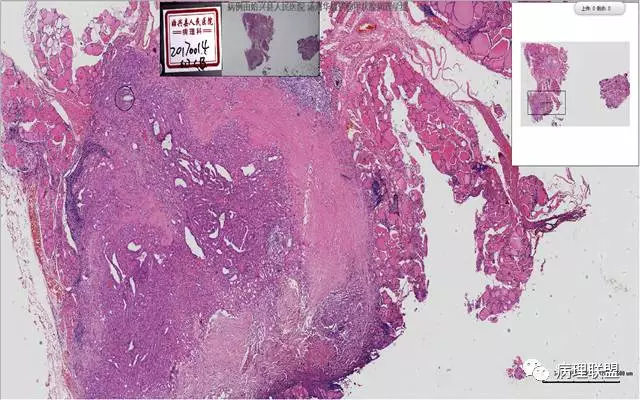

患者,女,45岁,发现双侧甲状腺肿物半月余。大体所见:左侧甲状腺肿物:4.3*5*4cm肿物一个,包膜完整,光滑,质脆,中央见出血。右侧甲状腺组织:3*1.6*1.5cm及1*1*0.8cm组织两块,其中较大的组织切开见内有0.8cm及1.2cm两个,质硬,灰白色,界不清,较小的,切开见灰黄色,质脆。